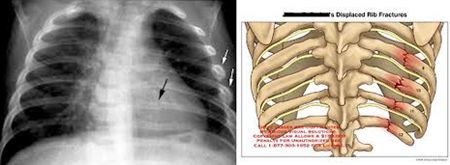

Κάταγμα πλευρών

Οι πλευρές του θώρακα μπορεί να υποστούν κάταγμα μετά από κάκωση από πτώση και άμεση πλήξη του θώρακα, αλλά συνήθως από σύνθλιψη σε τροχαίο ατύχημα όταν φοράς ζώνη.

Τα κατάγματα των πλευρών είναι πολύ επώδυνα, ενώ συνήθως δεν έχουν μεγάλη επίπτωση στην γενική υγεία. Σπάνια, όταν η κάκωση προέρχεται από ατύχημα, το σπασμένο πλευρό μπορεί να «τρυπήσει» το περίβλημα των πνευμόνων και να προκαλέσει πνευμοθώρακα.

Διάγνωση

Όταν υπάρχει κάταγμα στην επισκόπηση του θώρακα από τη ράχη, η πλευρά που πάσχει στην βαθειά αναπνοή δεν φαίνεται να κινείται όπως η φυσιολογική.

Εάν παρατηρηθεί αυτό, χρειάζεται ιατρική εξέταση για να διαπιστωθεί με ακουστικά, εάν ο πνεύμονας εκπτύσσεται (αναπνέει) ή έχει δημιουργηθεί πνευμοθώρακας.